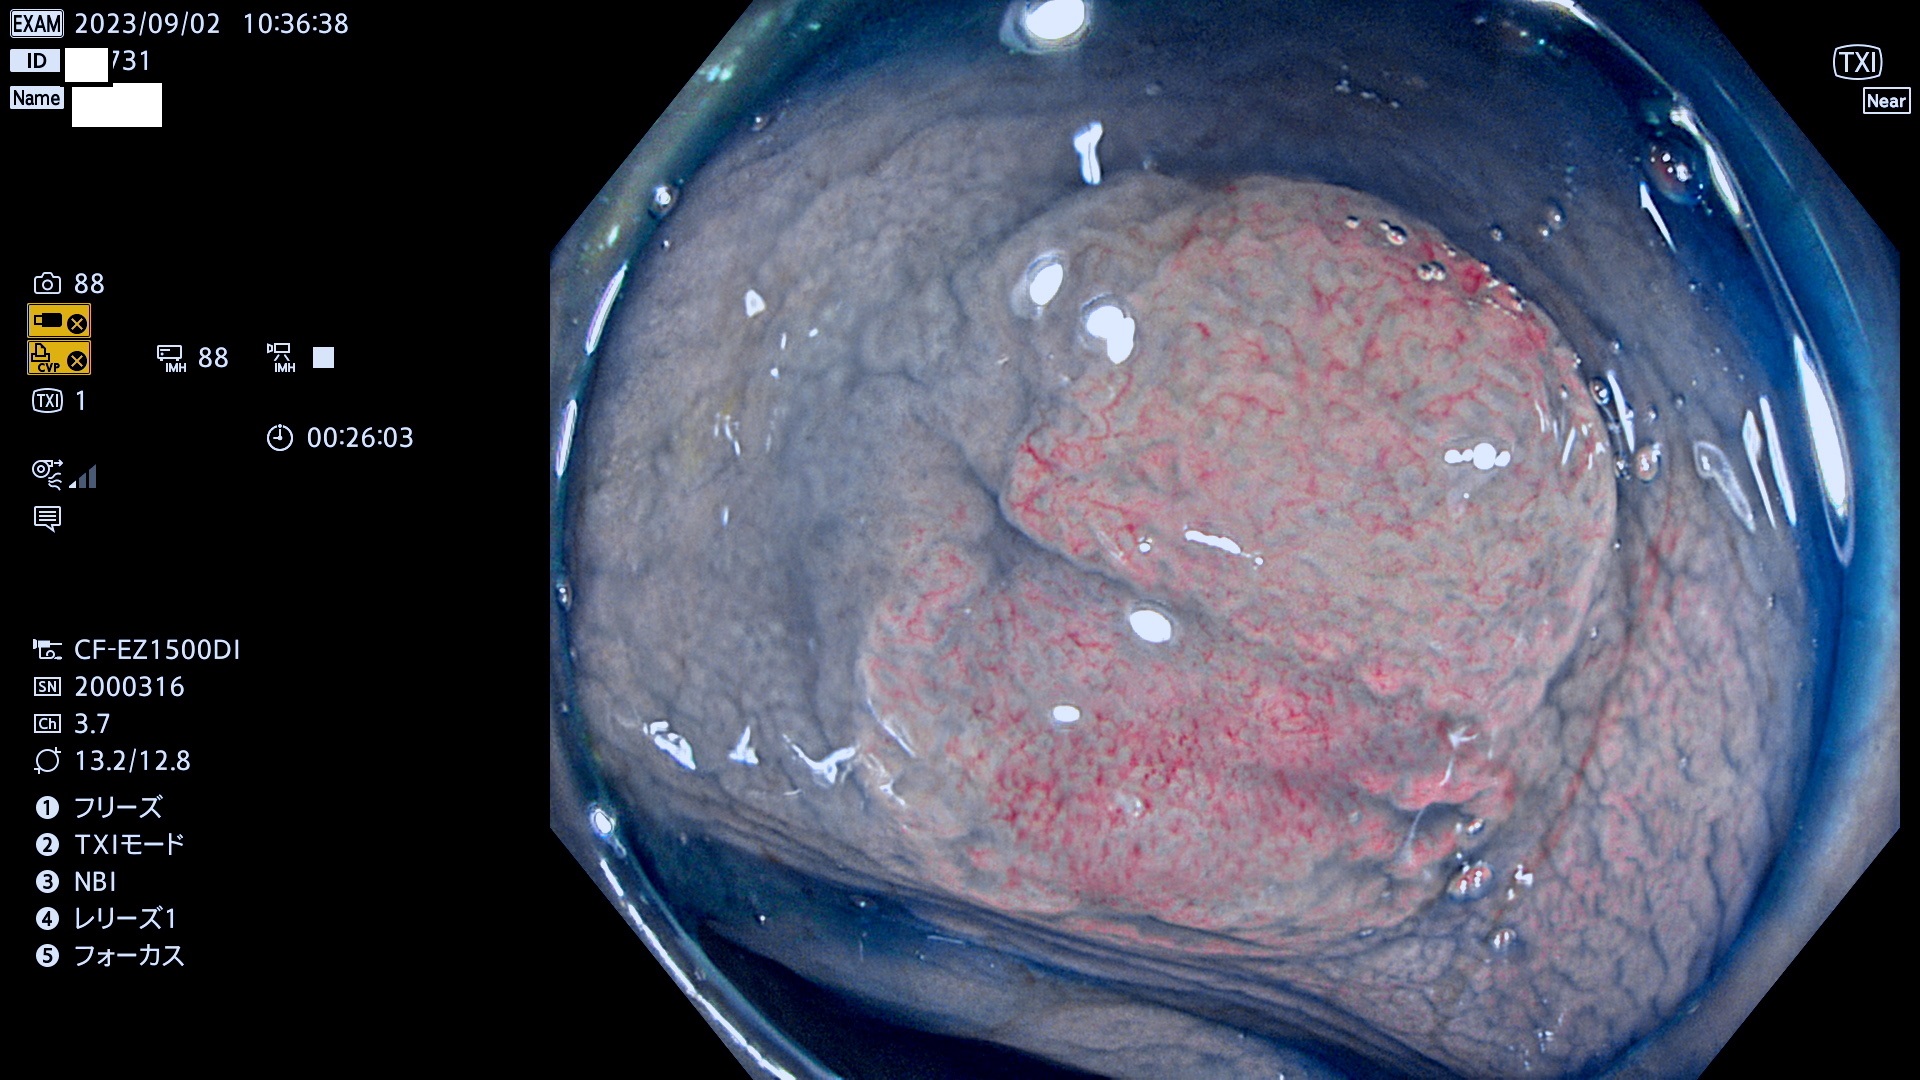

表面型腺腫(Flat Adenoma)の中で、完全に平坦な物をUb、陥凹している物をUcと呼びます。平坦隆起型(Ua)よりも、発見が難しく危険な病変です。このタイプは「内視鏡後・大腸癌の重要犯人」であり、この発見率は「腺腫発見率」よりも、重要な意味があります。

毎週の検査(木・金・土・日)に発見されたUb、Uc型・腺腫を、その週の日曜の夜にUPし1週間、提示します。

抽出の対象期間 2023年8月31日(木)〜9月3(日)の4日間(48件の検査)12件